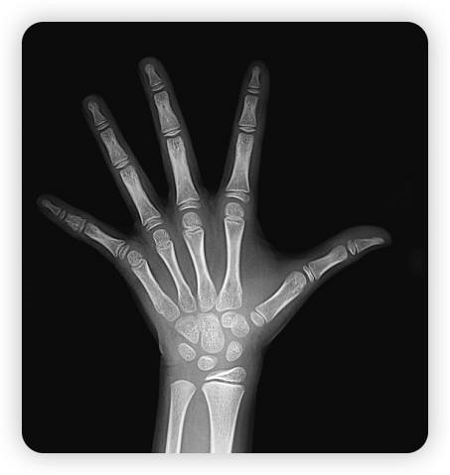

图片2

骨骺线尚未闭合状态